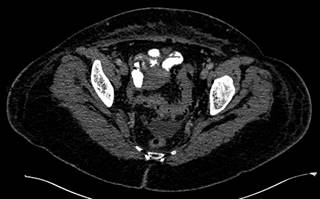

En el caso presentado, se observan datos de diverticulitis complicada a nivel de colon sigmoides, con trombo aéreo en vena sigmoidea adyacente y con extensión a vena mesentérica inferior (Figuras 1 y 2). Además, se visualiza defecto de llenado de la vena porta izquierda, secundario a trombo (Figura 3).

Figura 1: Tomografía computarizada en corte axial. Se observa proceso inflamatorio diverticular agudo a nivel de sigmoides.